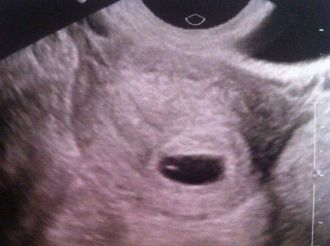

Suite à ma visite chez le médecin et pour me rassurer, direction le centre d’écho.

RDV prit à 14h00, RDV donné à 15h00, on n'y voit pas grand chose mais l'essentiel c'est que l'on distingue une vésicule vitelline et un point embryonnaire, son petit cœur devrait commencer à battre d'ici quelques jours.

Le sac gestationnel lui mesure 11mm. Une taille normale, tout parait bien se passer.